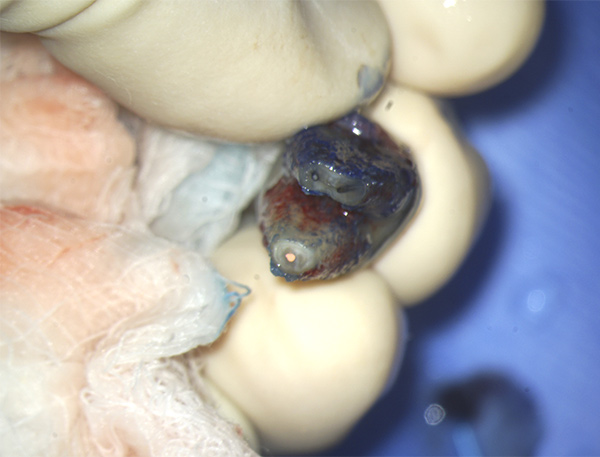

After objective confirmation of profound left mandibular anesthesia, tooth No. 18 was extracted and wrapped in gauze saturated with saline. Under a surgical microscope, the mesial and distal roots were resectioned 3 mm, and the root ends of both the mesial and distal roots were stained with methylene blue and irrigated with saline (Figure 6). Staining was noted around gutta-percha, but no fracture was observed on either root. Root-end ultrasonic preparation was made 3 mm in depth on the mesial and distal roots, and placement of a bioceramic root-end filling was completed.10 The entire root-end preparation and root-end fill was conducted outside the mouth within a 10-minute period.11 Also, during this time the socket of tooth No. 18 was gently curetted to remove granulomatous-type tissue. Not enough tissue could be removed for a biopsy. Tooth No. 18 was then properly reseated in the exposed socket (Figure 7) and sutured into place, and a final periapical radiograph was taken (Figure 8).

Extracted tooth N o. 18. Under surgical microscope, root-end resection and canal preparation

were performed prior to placement of root-end bioceramic filling.

Fig 6.